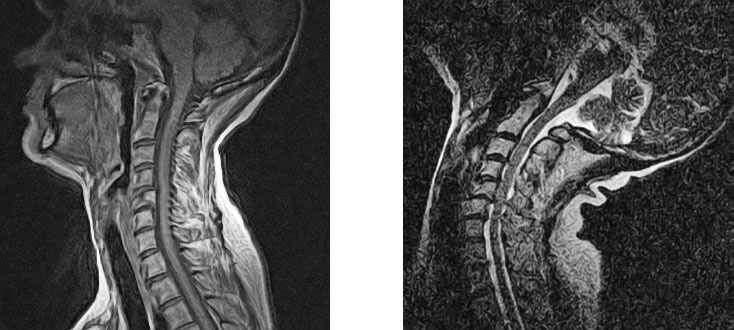

Специальные изменения в позах могут понадобиться людям с ампутированными конечностями, пациентам после инсульта и тем, у кого ограничены те или иные физические возможности. Например, при стенозе шейного отдела позвоночника не рекомендуется наклонять голову назад (изображение МРТ на рисунке 25 иллюстрирует возможный риск). Кроме того, обучая очень молодых людей, правильнее сосредоточиться на общей позе без дотошной корректировки деталей, поскольку она может быть воспринята как критика и лишит ученика всякого желания продолжать занятия. Для них гораздо полезнее выполнять упражнения с удовольствием, чем соблюдать все детали. В таких случаях компетентный учитель или терапевт станет ценным источником мудрости и безопасного обучения.

Рисунок 25. Запрокидывание головы значительно уменьшает диаметр и без того суженного позвоночного канала, приводя к спондилолистезу на уровне V шейного позвонка (удлиненный верхний позвонок – это II шейный). Сравните практически нормальный, слегка суженный канал в нейтральном положении (слева) и опасно сжатый спинномозговой канал при наклоне головы назад (справа). Опытные преподаватели с особой осторожностью следят за выполнением положений на сильную растяжку.